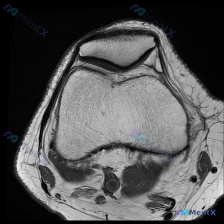

这是一张膝关节MRI-T1加权矢状位图像,核心发现整理如下:

- 骨骼结构:股骨远端、胫骨近端骨皮质完整,未见明确骨折线;股骨髁前上方可见边界清晰的局限性低信号区,伴随周围信号扭曲,是典型的金属伪影,提示此处有骨科内固定物

- 半月板:本次显示层面半月板形态完整,单一层面无法排除前后角细微损伤

- 交叉韧带:后交叉韧带走行连续,信号正常;前交叉韧带显示不清,位置和金属伪影吻合,高度提示既往有前交叉韧带(ACL)重建手术史

- 关节软骨:股骨、胫骨关节面软骨未见明显缺损、剥脱,无严重剥脱性骨软骨炎征象

- 关节与软组织:无明显关节腔积液,周围软组织无异常水肿